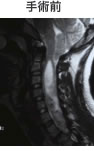

小脳が下垂し、脊柱管内に落ち込んでいます。

脊髄空洞を伴います。